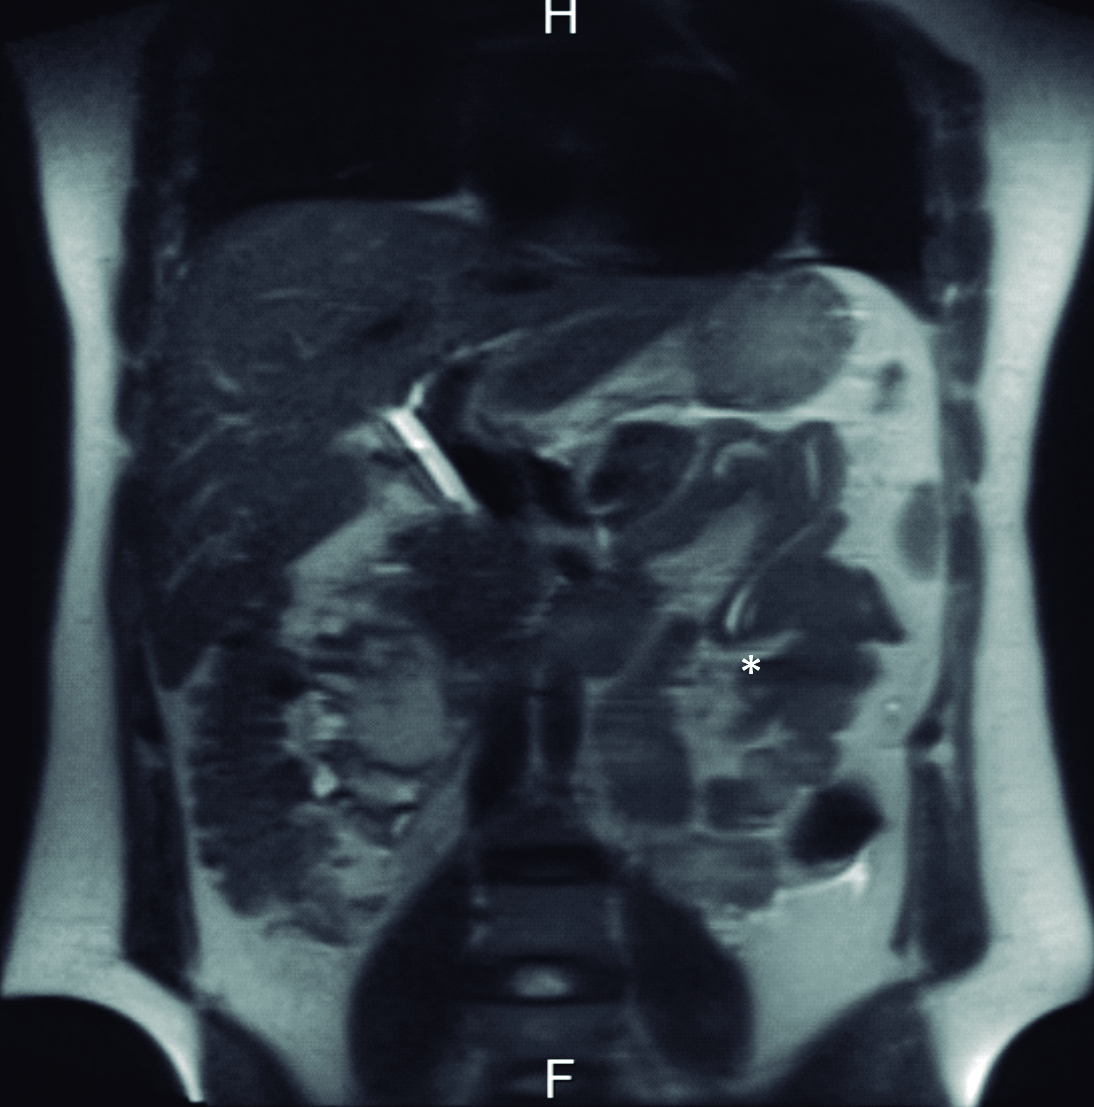

Figura 4. Resonancia Magnética

a y b) Imágenes en plano coronal potenciadas en T2 sin saturación grasa. A nivel de asas yeyunales proximales se identifican los parásitos como imágenes lineales ligeramente hiperintensas con un área central hipointensa (*).